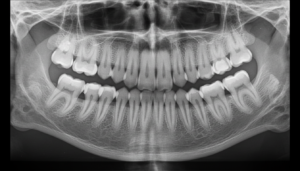

レントゲン撮影により、歯を支える骨がどれだけ残っているかを確認します。

骨が半分程度残っていれば、歯周病治療により歯を残せる可能性が高くなります。骨が3分の1以下でも、再生療法により骨を増やすことができる場合があります。

歯科用CTやセファロレントゲンなどの検査機器を備え、拡大鏡で細かなところまで確認しながら診断を行います。